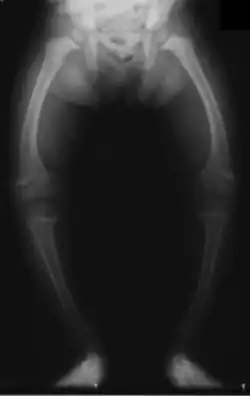

Les déformations osseuses prédominent aux membres inférieurs (aggravées par la station debout et la marche), en restant plus discrètes aux membres supérieurs. L'aspect le plus fréquent est le genu varum (jambes arquées en parenthèses) ; plus rare est la déformation inverse ou genu valgum (jambes arquées en X). La crête du tibia peut faire saillie « en lame de sabre ». Ces déformations indiquent un rachitisme sévère. Plus tardivement, une coxa vara (déplacement de la tête du fémur) peut apparaitre avec une « démarche en canard ».

Ces déformations retentissent sur le bassin osseux qui s'aplatit ou se rétrécit. Chez les filles, c'est une future source éventuelle de dystocie osseuse (accouchement difficile par bassin étroit), cause historique importante de décès maternel lors de l'accouchement.

La radiologie confirme le diagnostic, et il est inutile de les multiplier. Le défaut de minéralisation des os longs s'observe particulièrement sur les radiographies de face d'un poignet et des genoux : retard ou irrégularités des points d'ossifications attendus pour l'âge (maturation squelettique), lignes métaphysaires irrégulières donnant un aspect « en toit de pagode », la corticale de la diaphyse est amincie, la densité osseuse est diminuée donnant un aspect vermoulu. Les os longs s'incurvent.

Enfants d'une même famille souffrant de rachitisme, Paris, vers 1912.